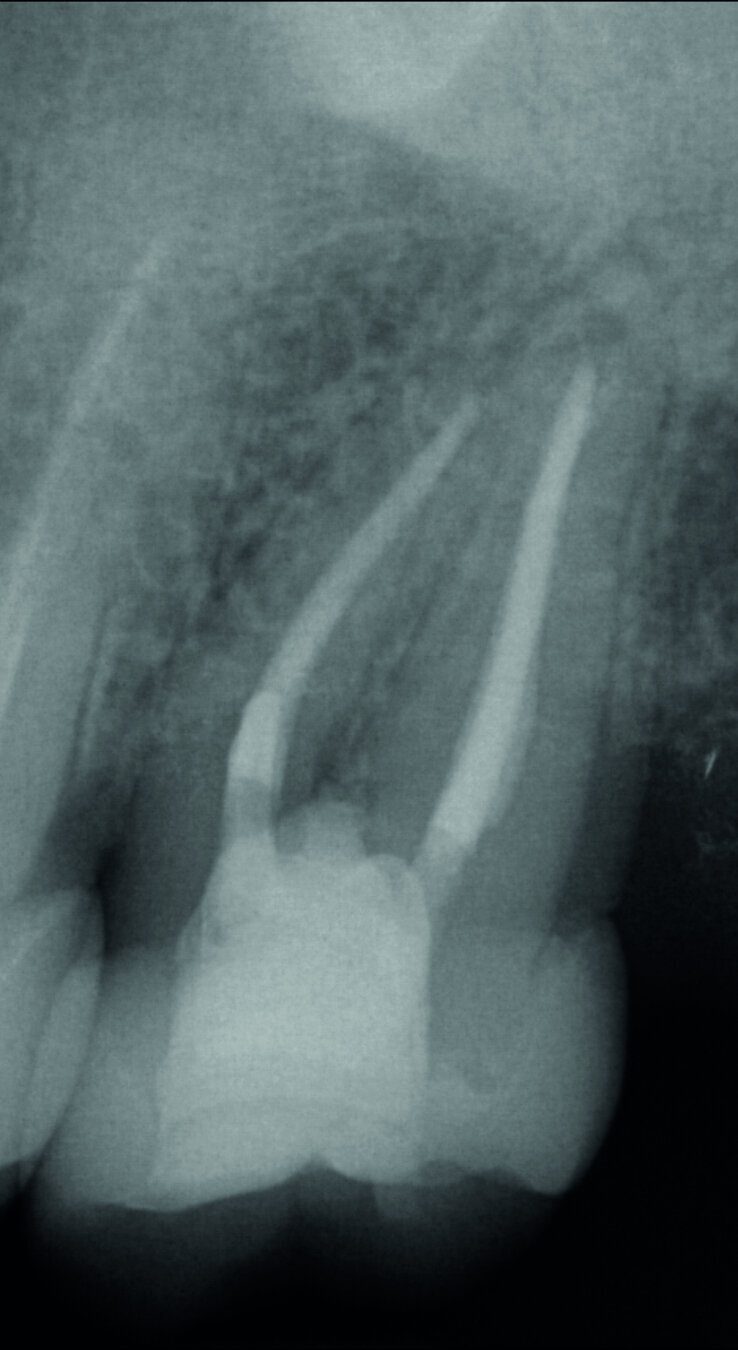

À gauche : Maîtres cônes mis en place dans le canal ; à droite : Radiographie des maîtres cônes pour confirmer la longueur de travail définie. (Photos : Dr Georg Benjamin)

Fig. 10 : Radiographie des maîtres cônes pour confirmer la longueur de travail définie.

Le matériau d’obturation du canal radiculaire (Figs. 9 et 10) a été enfoui aussi profondément que possible afin de parvenir à une surface de rétention adhésive maximale pour la fermeture post-endodontique, puis un sablage par Al2O3 a été réalisé (Fig. 11). Ensuite, everX Flow de teinte translucide (Bulk) a été utilisé et a comblé un hiatus dans mon protocole de traitement. Le produit s’écoule très bien, sans formation de bulles, dans la profondeur des canaux et il permet donc l’obturation des petits canaux radiculaires avec un matériau composite renforcé en fibres de verre (glass fibre reinforced material, FRC). Dans ce cas, j’ai utilisé everX Posterior, de viscosite plus élevée, selon la technique dite de chasse-neige.